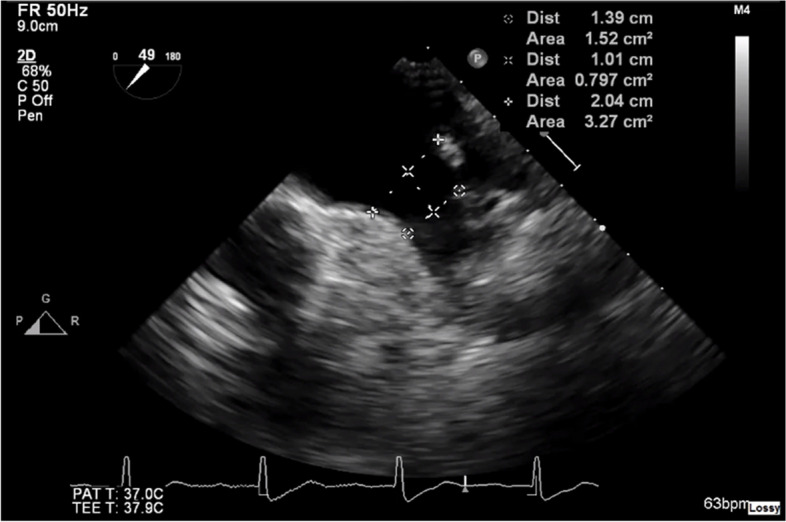

The heterogeneous anatomy of the left atrial appendage (LAA) necessitates preprocedural imaging essential for planning of percutaneous LAA occlusion (LAAO) procedures. While transoesophageal echocardiography (TOE) remains the gold standard, cardiac computed tomography (CT) is becoming increasingly popular. To address the lack of consensus on the optimal imaging modality, we compared the outcomes of preprocedural TOE versus CT for LAAO procedure planning. A retrospective single-center cohort study of all LAAO procedures was performed to compare the outcomes of patients receiving preprocedural TOE versus those receiving CT. The primary outcome was procedural success and rate of major adverse events. The secondary outcomes were total procedure time, rate of device size change, and maximum landing zone diameter. A total of 64 patients was included. Of these, 25 (39.1%) underwent TOE and 39 (60.9%) underwent CT. There was no significant difference in the procedural success rate (96.0% vs. 100%, P = 0.39) or major adverse event rate (4.0% vs. 5.1%, P > 0.99) between TOE and CT patients. Compared with TOE, CT was associated with significantly shorter median procedure time (103 min vs. 124 min, P = 0.02) and a lower rate of device size change (7.7% vs. 28.0%, P = 0.04). Compared to CT, TOE was associated with a significantly smaller mean maximum landing zone diameter (20.8 mm vs. 25.8 mm, P < 0.01) and a higher rate of device upsizing (24.0% vs. 2.6%, P = 0.01). No significant difference in detected residual leak rates was found between TOE and CT (50.0% vs. 52.2%, P > 0.99). Planning of LAAO procedures with CT is associated with a shorter total procedure time and a lower rate of device size change and is less likely to underestimate the maximum landing zone diameter.